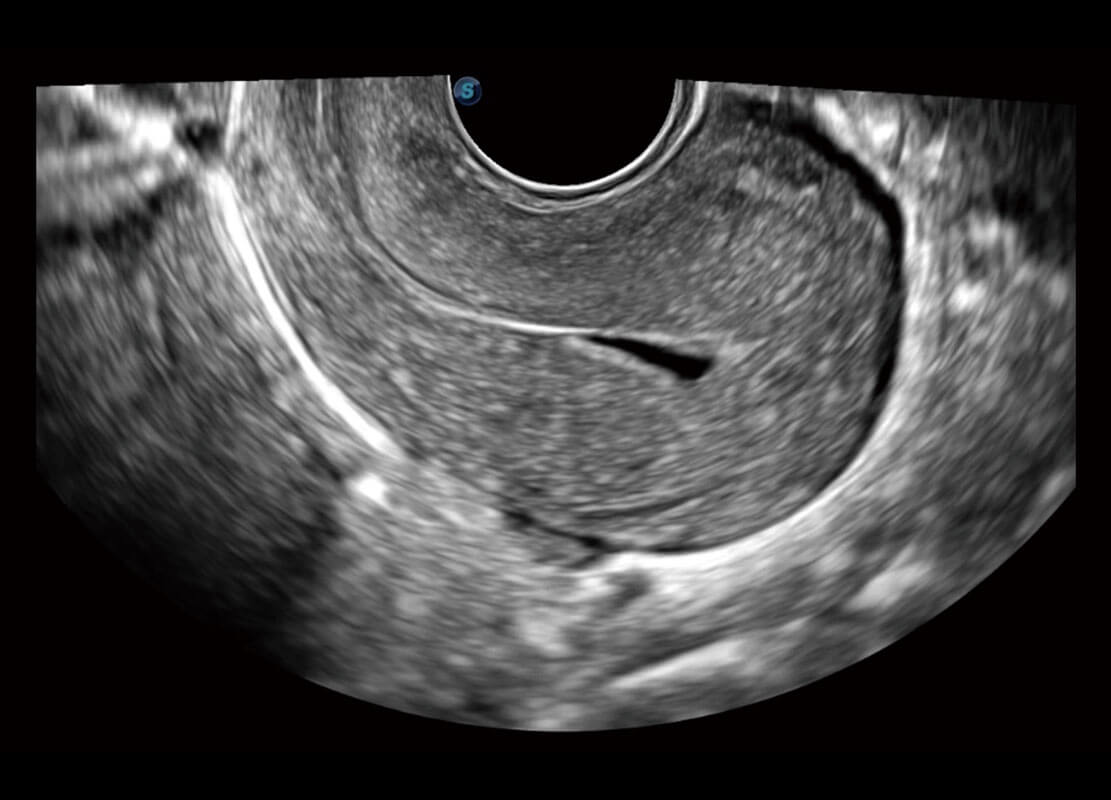

P60優(yōu)異的圖像質(zhì)量搭載專(zhuān)科探頭,在婦科基礎(chǔ)疾病的診斷、卵泡生長(zhǎng)的監(jiān)測(cè)、輸卵管通暢情況的判別等方面為您提供生殖應(yīng)用方案。

腔內(nèi)婦科-宮腔分離

腔內(nèi)婦科-卵巢

腔內(nèi)三維-宮內(nèi)節(jié)育器

腔內(nèi)三維-光影成像